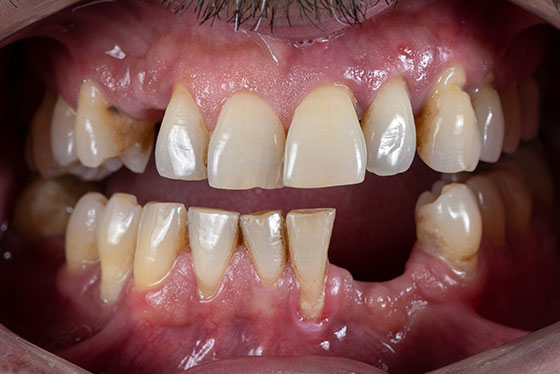

虫歯や歯周病で多くの歯を失ってしまうと、毎日の生活の中で、さまざまなつらさを抱えやすくなります。

「インプラントならしっかり噛めるようになるかもしれない」と感じていても、失った歯すべてを1本ずつインプラントにするとなると、本数も多く、手術や費用の負担がとても大きくなってしまいます。

そこで当院では、多くの歯を失った方に対して、負担をできるだけ抑えながら「しっかり噛めるお口」を目指す方法として、「All-on-4(オールオンフォー)」をご提案しています。